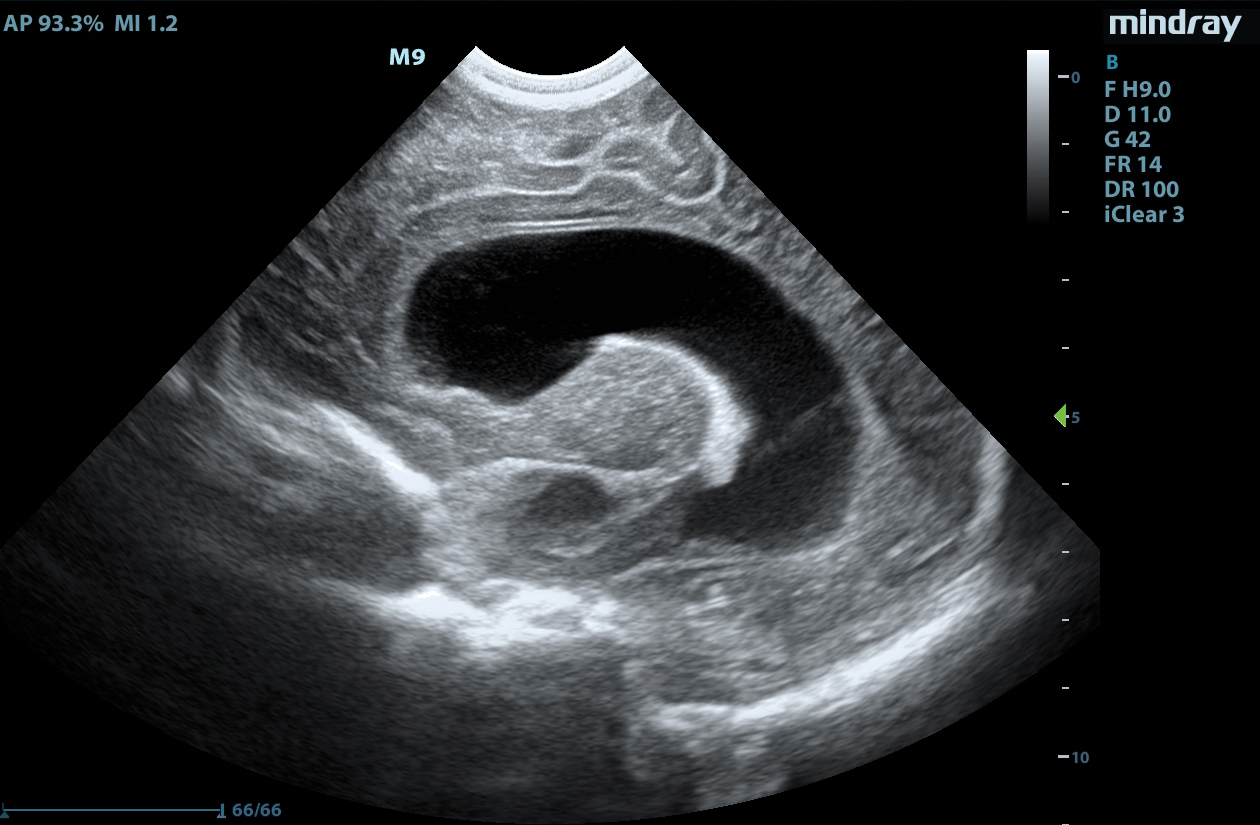

The M9 Ultrasound System Ruby Edition offers a fully-featured, compact ultrasound solution for your most challenging point-of-care exams. Delivering image clarity and advanced capabilities previously only available on larger, cart-based systems, the M9 System defines the new standard for intelligent performance in a mobile, laptop design.

Equipped with single crystal transducers and 3T™ technology for a wide range of exams, the M9 System is a versatile platform for advanced imaging in the vascular lab, emergency departments, critical care environments, and anesthesia practices. The System’s slim profile and ergonomic design allow for effortless flexibility and mobility. Whether it be ultrasound guided procedures at the patient’s bedside or transesophageal echocardiography (TEE) imaging in the critical care unit, this platform can do it all.